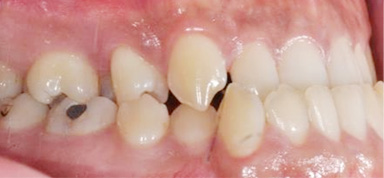

주걱턱으로 앞니가 서로 거꾸로 물리고 어금니가 제대로 물리지 않는 남환, 타 병원에서 양악 수술 진단을 받고 내원하셨습니다.

고운미소에서 교정용 미니스크류를 이용하여 아래 치열은 후방이동, 위 치열은 전방으로 이동하는 치료를 진행하였습니다.

위턱에 비해 아래턱이 크고 전방에 위치, 우측으로 변위된 비대칭을 보입니다.